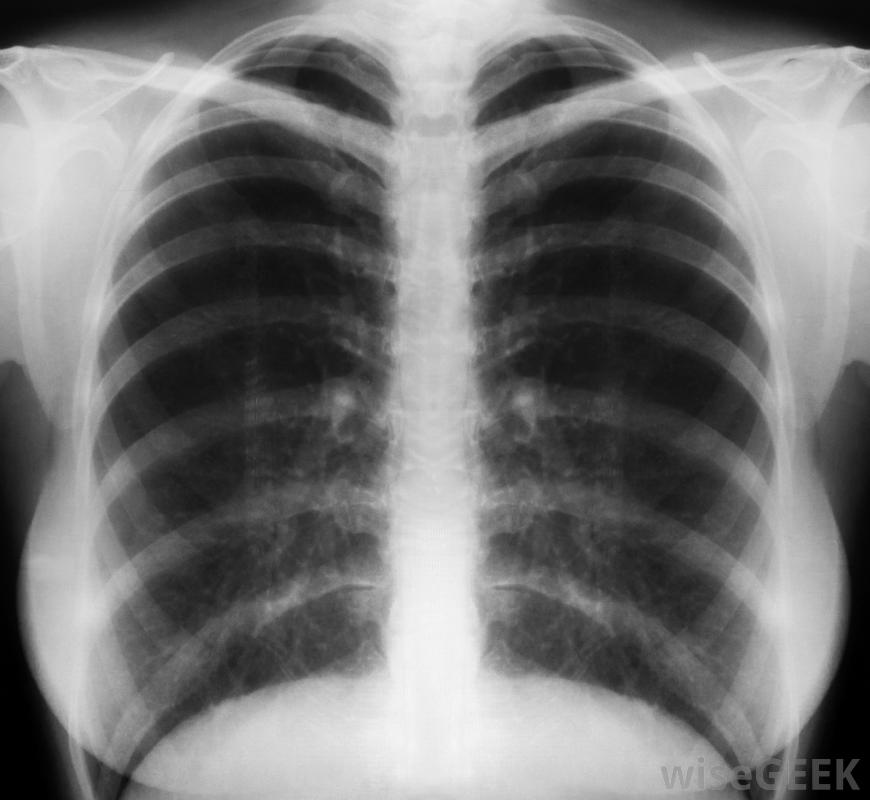

心臟增大是指心臟增大。通常稱為心臟肥大,它不是一種疾病或紊亂,而是另一種通常是嚴重的中等疾病的癥狀。心臟增大可能是一種暫時的情況,會自行消失,也可能是需要內科治療的慢性問題隨著心臟增大,胸部x光可以暴露其他可能導致心臟增大的情況。很多時候心臟增大沒有癥狀。當出現癥狀時,可能會很嚴重。心律失常,也叫心律失常,是心臟病的一種常見副作用。其他癥狀可能是呼吸困難增加,呼吸急促和頭暈。過度咳嗽也可能是一種癥狀。更嚴重的癥狀包括嚴重的胸痛、頭暈或暈厥。這些癥狀也可能是心臟病發作的征兆心臟增大會導致心臟增大。心臟增大的癥狀可能包括胸痛和呼吸困難心臟通常會因為受到額外的壓力而變大,有時這可能是由受傷引起的暫時情況,但有時是由于更嚴重的情況高血壓、心臟瓣膜病、甲狀腺疾病、先天性心臟病和貧血都是導致心臟增大的常見原因。另一個原因是心臟病,即心肌無力。隨著肌肉的衰弱程度增加,它可能會擴大,作為補償。有時體內過量的元素會導致心臟問題。血色素沉著癥是體內鐵的堆積,是心臟增大的另一個常見原因。淀粉樣變性也是如此,淀粉樣變性是心臟內蛋白質的堆積高血壓通常會導致心臟增大。醫生無法通過基礎檢查來確定某人是否心臟增大,這意味著必須進行額外的檢查才能發現。大多數情況下,他們會對胸部進行x光檢查。除了發現心臟是否增大外,胸部x光片還可以揭示其他可能導致心臟增大的情況。通常在x光片之后,會進行額外的檢查病人通常要做心電圖來監測心臟的電活動,同時還要做一個超聲心動圖來產生和分析心臟的視覺圖像。計算機斷層掃描和磁共振成像掃描,通常稱為CT和MRI掃描,有時也用于確定患者心臟狀況的性質,還需要進行血液檢查一旦確診,首先要通過治療引起心臟增大的潛在疾病來矯正心臟腫大。可以開一些恢復心臟力量、降低血壓或控制甲狀腺水平的藥物,根據診斷結果,有時手術也是必要的。起搏器和心臟瓣膜置換術有時可以糾正與心臟增大相關的疾病。醫學專業人員可能會檢查X光片心臟增大的跡象。